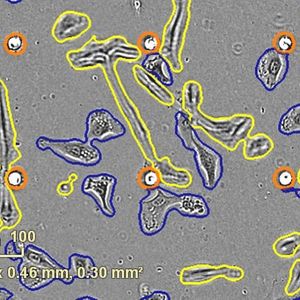

OCT 24, 2023Clinical & Molecular DXWhen a sample of tissue is analyzed, it is normally cut into thin slices that can then be treated and assessed in variou ...